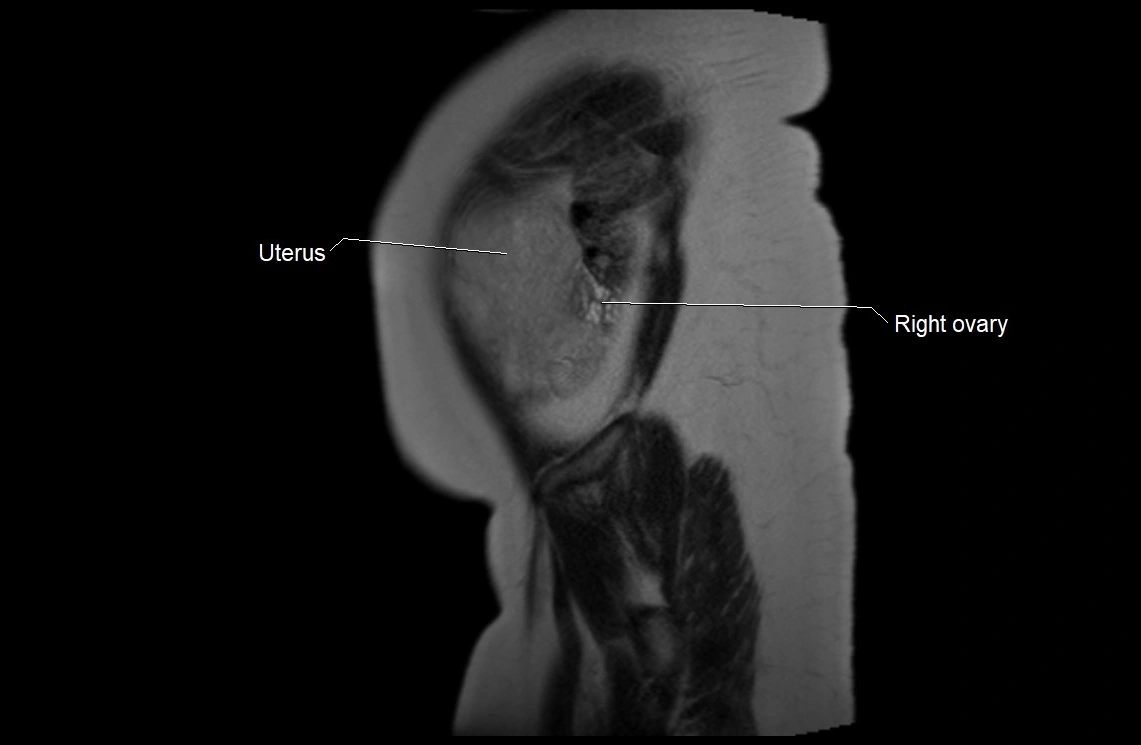

MRI image

image